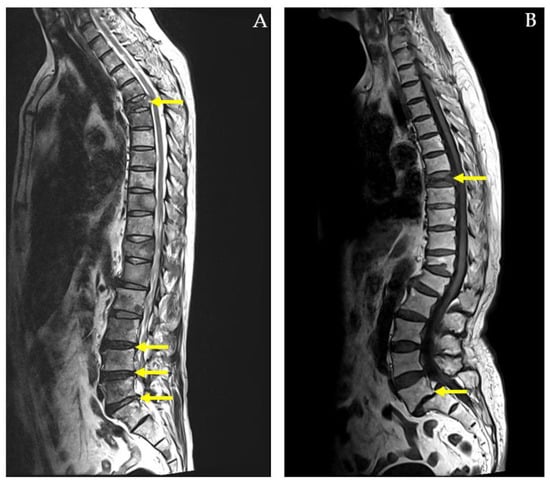

Number of Spine Pain Regions: The number of painful regions in the spine was assessed using the MRI report, which offers an objective measure of pain distribution and severity. This clinical examination identifies areas of tenderness and helps differentiate between conditions involving localized versus widespread spinal involvement. For example, a 73-year-old female with herniated intervertebral discs (HIVDs) at the C5-C6-C7 and L4-L5-S1 levels had six identified spine pain regions (Figure 2A). In contrast, a 77-year-old male with a compression fracture at T12 had only one identified spine pain region (Figure 2B).

Figure 2. MRI whole-spine imaging demonstrating herniated intervertebral discs (HIVDs) indicated by yellow arrow in (A) and compression fracture indicated by white arrow in (B).